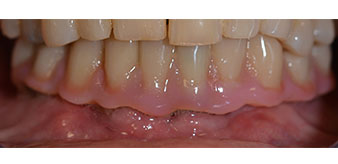

The 64-year-old patient presented with residual dentition of teeth 38, 33 and 43 and a clasp denture in the mandible (Fig. 1 and 2).